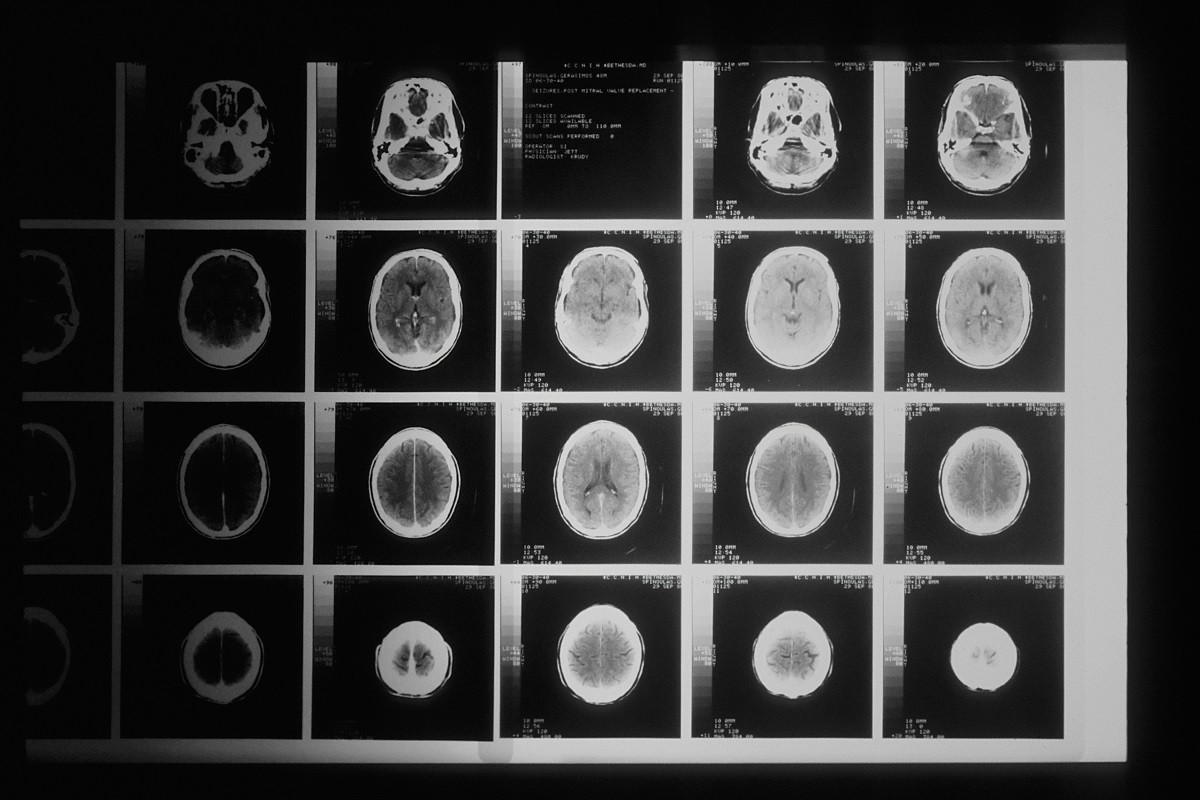

Η μελέτη, που δημοσιεύθηκε στο Journal of Sport and Health Science, συνέκρινε τα αποτελέσματα μαγνητικής τομογραφίας ατόμων που ακολούθησαν σταθερά πρόγραμμα αερόβιας άσκησης για έναν ολόκληρο χρόνο με εκείνα μιας ομάδας ελέγχου που δεν γυμναζόταν τακτικά.

Όταν ολοκληρώθηκε το έτος, οι μαγνητικές τομογραφίες έδειξαν ότι οι εγκέφαλοι της ομάδας που ασκούνταν φαίνονταν περίπου ένα χρόνο νεότεροι σε σύγκριση με εκείνους της ομάδας ελέγχου.